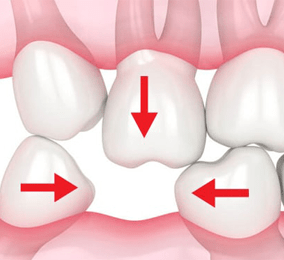

HẬU QUẢ KHI KHÔNG TRỒNG RĂNG KỊP THỜI

Không trồng răng implant kịp thời có thể gây tiêu xương hàm, khiến khuôn mặt biến dạng và lão hóa sớm. Ngoài ra, mất răng còn ảnh hưởng nghiêm trọng đến thẩm mỹ, khiến bạn tự ti khi giao tiếp.